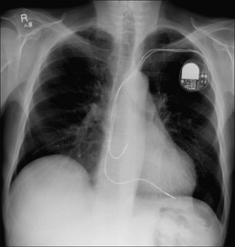

The electrical stimulus which causes the heart to contract originates in the sinoatrial (SA) node in the right atrium. This incites the two atria to contract via a conduction pathway. The impulse also passes from the SA node to the atrioventricular (AV) node and thence along the bundle of His to the right and left ventricles (Fig. 12.1).

Figure 12.1 Conducting system of the heart:1 = SA node; 2 = AV node;3 = right bundle branch;4 = left bundle branch. The position of the foramen ovale is shown as a ring inferior to the SA node. Note the additional electrical pathway also originating in the SA node. This carries electrical impulses to the right and left atria.